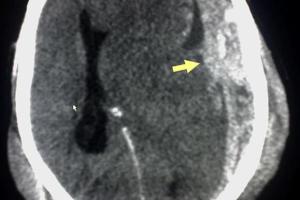

Tratamiento del hematoma subdural crónico

Leer más